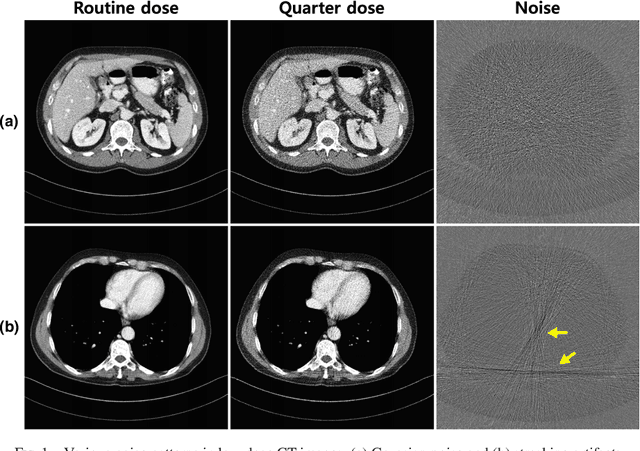

Abstract:Due to the potential risk of inducing cancers, radiation dose of X-ray CT should be reduced for routine patient scanning. However, in low-dose X-ray CT, severe artifacts usually occur due to photon starvation, beamhardening, etc, which decrease the reliability of diagnosis. Thus, high quality reconstruction from low-dose X-ray CT data has become one of the important research topics in CT community. Conventional model-based denoising approaches are, however, computationally very expensive, and image domain denoising approaches hardly deal with CT specific noise patterns. To address these issues, we propose an algorithm using a deep convolutional neural network (CNN), which is applied to wavelet transform coefficients of low-dose CT images. Specifically, by using a directional wavelet transform for extracting directional component of artifacts and exploiting the intra- and inter-band correlations, our deep network can effectively suppress CT specific noises. Moreover, our CNN is designed to have various types of residual learning architecture for faster network training and better denoising. Experimental results confirm that the proposed algorithm effectively removes complex noise patterns of CT images, originated from the reduced X-ray dose. In addition, we show that wavelet domain CNN is efficient in removing the noises from low-dose CT compared to an image domain CNN. Our results were rigorously evaluated by several radiologists and won the second place award in 2016 AAPM Low-Dose CT Grand Challenge. To the best of our knowledge, this work is the first deep learning architecture for low-dose CT reconstruction that has been rigorously evaluated and proven for its efficacy.